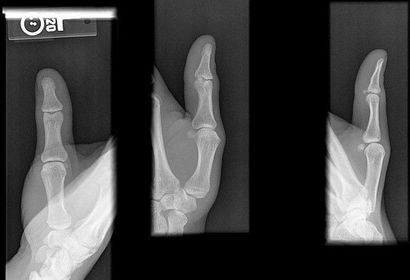

| AP Thumb | metacarpals overlapping thumb |

| Oblique Thumb | slightly overrotated foreshortened distal phalanx |

| Lateral Thumbs | should be concave to one side only and straight on the other images are not truly lateral |

| AP Thumb Criteria | ANATOMY: entire digit including trapezium CRITERIA: equal concavity on both sides of digit open joint spaces no superimposition from adjacent bones POSITIONING: CR perpendicular @ 1st MCP joint |

| Oblique Thumb | ANATOMY: entire digit including trapezium CRITERIA: more concave to the side farthest from IR open joint spaces no superimposition from adjacent bones POSITIONING: CR perpendicular @ 1st MCP joint |

| Lateral Thumb | ANATOMY: entire digit including trapezium CRITERIA: most concave to one side, while the other is straight open joint spaces no superimposition from adjacent bones POSITIONING: CR perpendicular @ 1st MCP joint |